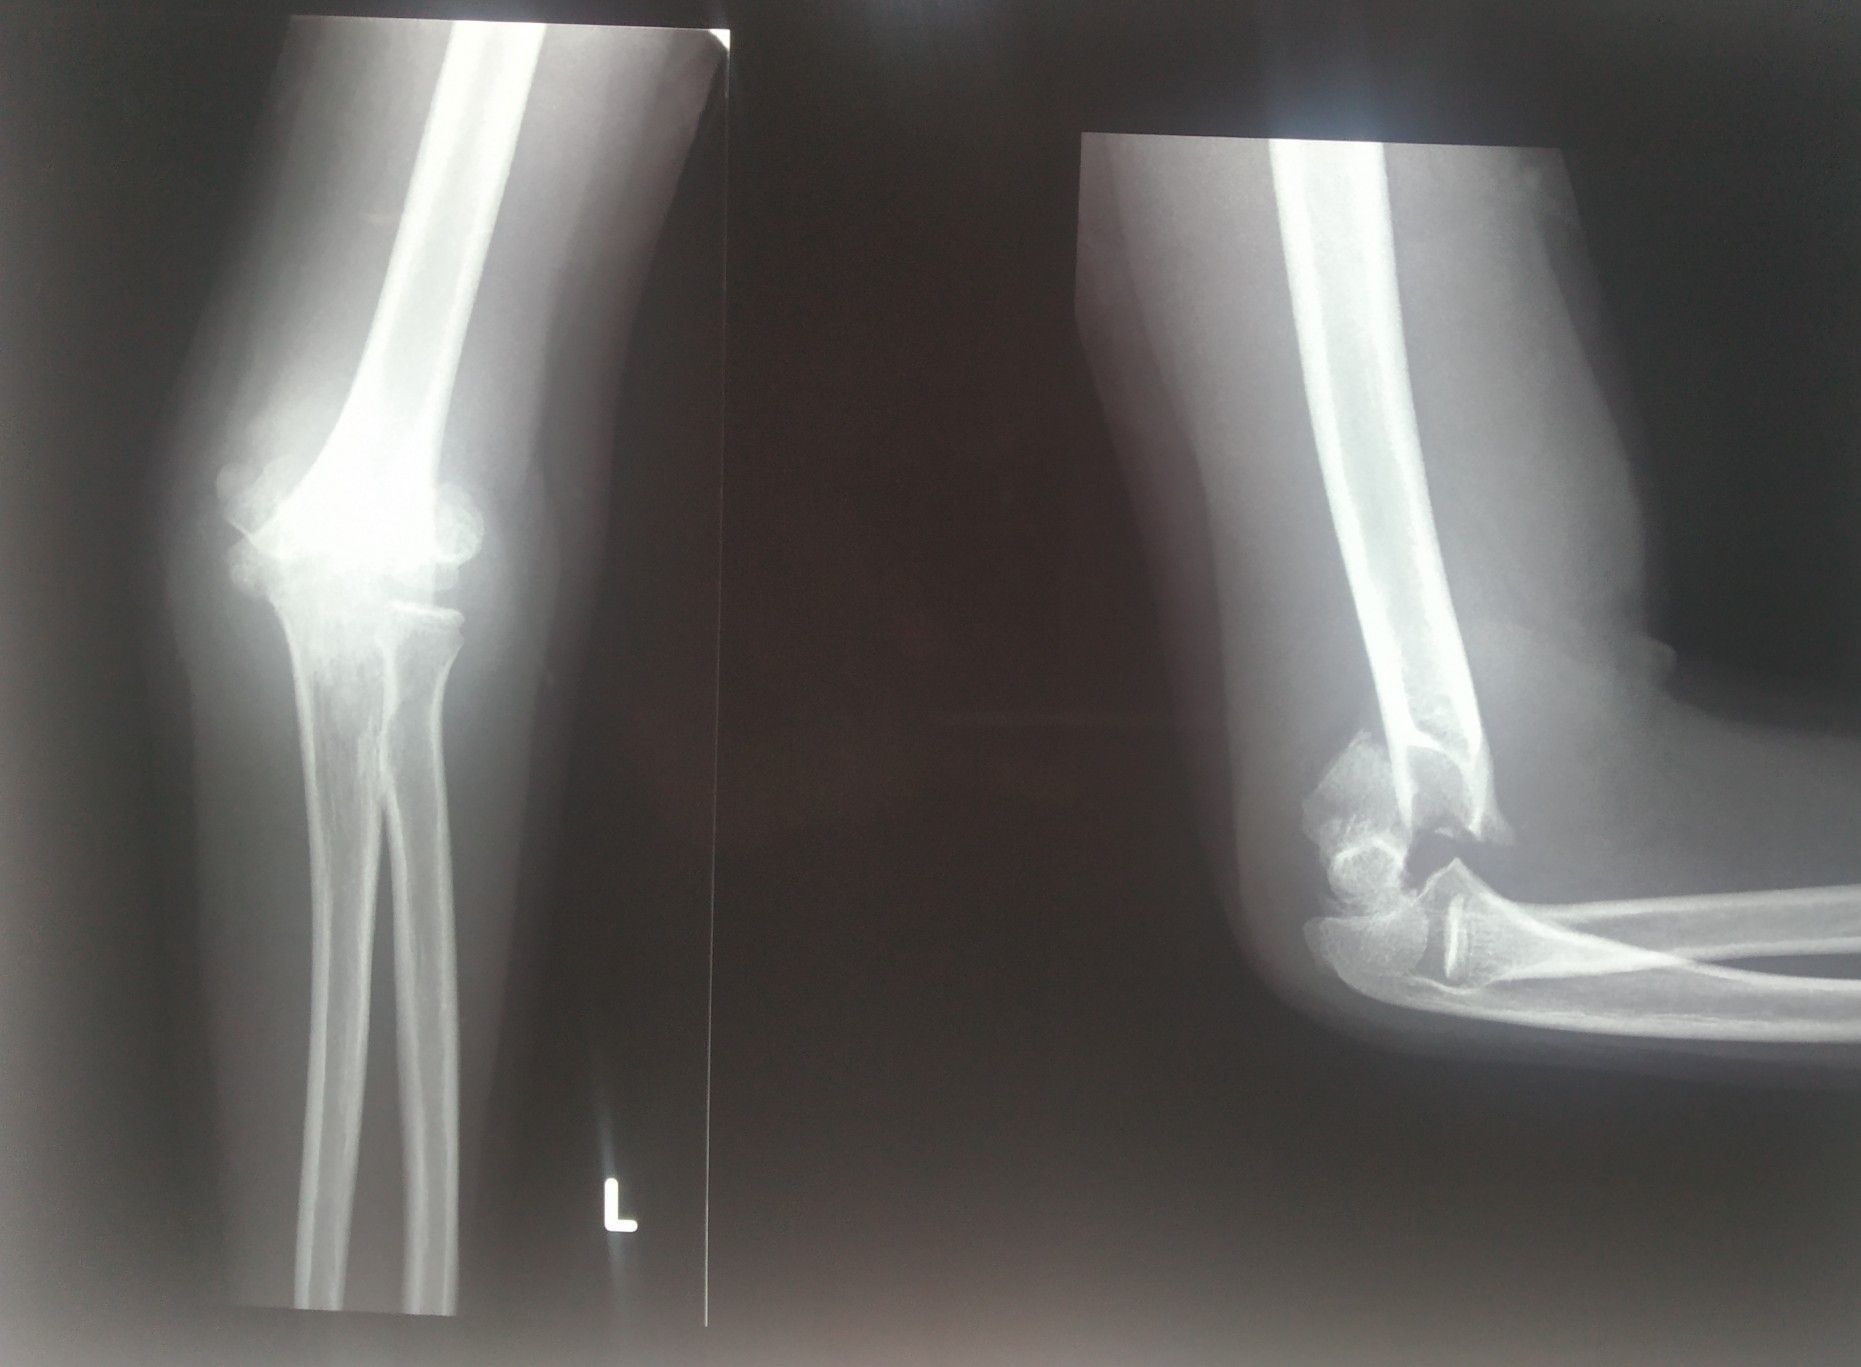

supracondylar fracture

Xray

Orthopaedics

Fracture

Elbow

Supracondylar